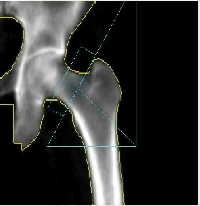

Kość udowa |

W przypadku pomiarów kolejnych aparat LUNAR PRODIGY PRIMO z oprogramowaniem enCORE porównuje procentowo wyniki z poprzednimi oznaczeniami i umiejscawia je na wydruku, który otrzymuje pacjent. Standardowo zaleca się wykonywanie takich oznaczeń co 12 miesięcy, na tym samym aparacie , w tej samej lokalizacji oraz najlepiej przy tej samej osobie obsługującej urządzenie (najmniejszy błąd pomiarowy).

Wg zaleceń Międzynarodowego Stowarzyszenia Densytometrii Klinicznej (ang. International Society for Clinical Densytometry) z roku 2007 pomiar gęstości mineralnej kości (ang. BMD – Bone Mineral Density) kręgosłupa lędźwiowego L1 – L4 oraz kości udowej (ang. total hip) jest zalecany do łącznej oceny z wynikami morfometrycznym metodą DXA (VFA ang. Vertebral Fracture Assessment) oraz kliniczną oceną czynników ryzyka złamań. |

Obecnie uznaje się, że podstawowym i preferowanym miejscem oceny densytometrycznej powinno być badanie nasady bliższej kości udowej, głównie z oceną szyjki kości udowej oraz oceną części lędźwiowej kręgosłupa w obrębie kręgów L1-L4.

Podczas badania przeprowadzanego w pozycji leżącej na plecach zostaje wykonany pomiar gęstości mineralnej kości (ang. BMD – Bone Mineral Density) w całej kości udowej (ang. total hip) oraz w szyjce kości udowej (ang. femoral neck). Mimo standardowego wykonywania pomiaru BMD jednej kości udowej (lewej lub prawej) istnieje możliwość jednoczesnego pomiaru obu kości udowych (ang. dual femur) oraz oznaczenia długości szyjki kości udowej (ang. hip axis lenght), która jest niezależnym czynnikiem ryzyka złamania.

Badanie zostaje wykonane przy niskich względem klasycznej metody RTG awkach promieniowania jonizującego. Jest więc bezpieczniejsze i mniej szkodliwe oraz istnieje możliwości ponownego badania w krótkim czasie. Poza tym zastosowanie najnowszych rozwiązań technologicznych gwarantuje wysoką jakość obrazu oraz standaryzowaną procedurę pomiaru.